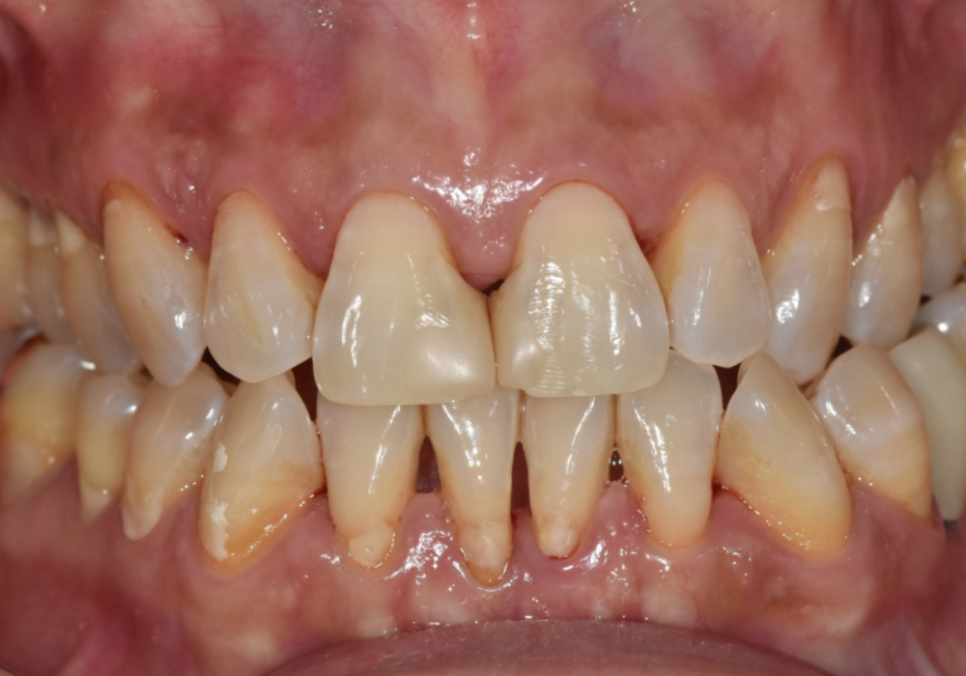

환자분의 또 다른 고민은

치아 색상이 예전보다

어둡고 누렇게 보인다는 점이었습니다.

우리 치아는

겉을 감싸는 하얀 법랑질(enamel)과

그 안쪽의 노란빛을 띄는 상아질(dentin)로

이루어져 있습니다.

고덕동 치과 누런 이, 앞니 사이 틈, 잘못된 관리 때문일까?

법랑질은 우리 몸에서

가장 단단한 조직이지만,

평생 수천 번의 저작 운동과

음식, 생활 습관, 외부 자극을 반복적으로 받으며

조금씩 마모될 수밖에 없습니다.

이 과정에서

법랑질의 두께가 얇아지면

안쪽의 상아질 색이 비쳐 보이게 되고,

치아는 점점

어둡고 누렇게 보이게 됩니다.

이처럼 노화로 인한 치아 변색은

표면 착색과는 원인이 다르기 때문에

전문가 치아미백만으로는

개선이 어려운 경우가 많습니다.